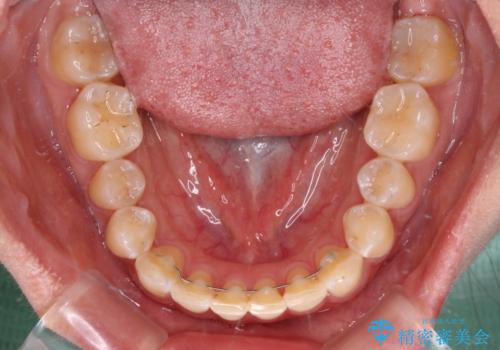

- 矯正装置

- 審美装置

- 上下前歯隙間と正中のズレを改善したいとのことで来院された患者様です。

自己管理を減らしたいとのことで、ワイヤー装置による矯正治療を行うこととしました。

正中がなかなか合わずに、2年近くの治療期間を要しました。